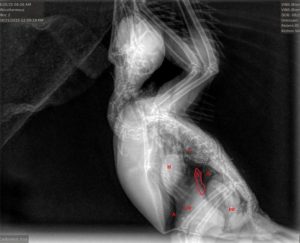

Photo: Purple Gallinule

Rehab Fact: Avian Malaria

When you think of malaria, you probably think of the tropics – after all, that’s where humans can be infected. For birds though, malaria is worldwide, present on every continent except Antarctica (at least for now). Birds across the world have evolved with dozens of malaria species, and most of the time are only subtly affected. However, changing infection and environmental dynamics have altered this balance, sometimes in dramatic ways. Invasive malaria has caused the extinction of about a third of Hawaii’s honeycreeper species since the late 1800’s, and other introduced strains, global warming and environmental toxins have made malaria infections more dangerous over time. But before we get into how it affects Vermont’s birds, what exactly is malaria?

Malaria is caused by a single celled parasite in the genus Plasmodium, that has a complex life cycle involving both mosquitoes and vertebrate hosts. Briefly, an infected mosquito bites a bird, human, or other animal, and the parasites are transmitted in the saliva. They initially undergo asexual reproduction in tissue cells, then invade red blood cells. Once the blood is infected, gametes, the mature parasites, can be taken up by a mosquito to continue the infection cycle. A second form, called schizonts, develop into clusters of smaller forms called sporozoites, and when the schizont is mature it ruptures the red blood cell, allowing the sporozoites to spread and infect other red blood cells. Destruction of red blood cells leads to anemia, which can cause weakness, circulatory disorders and kidney damage. The red blood cell turnover also leads to a greatly enlarged liver and spleen, which can put pressure on the air sacs and contribute to respiratory difficulty. Somewhat unique to birds, tissue stages can also cause severe disease or death, particularly when the cells that line blood vessels become infected and swollen, which can lead to blockages that prevent blood flow to parts of the brain. Finally, immune compromise from malaria infection can lead to high rates (>40%) of severe bacterial and fungal coinfections, making treatment substantially more difficult.

So what birds in Vermont are affected by malaria? It was first discovered in Northeastern common loons in 2017, and has caused mortalities each year, making it an emerging disease, although luckily it hasn’t seemed to cause major impacts so far. The more widespread effect is in passerines, which is where nearly all cases have been seen in CWBR. It is primarily a disease of juvenile birds, particularly American robins, corvids and grackles. In fact, in some years it is a leading cause of infectious disease deaths in robins, with 7 cases and 5 deaths in 2025- making it responsible for 25% of deaths in care for robins this year. I suspect that it is an underrecognized disease in juvenile passerines, for a variety of reasons: many rehabilitators either don’t or can’t do bloodwork on songbirds, or don’t perform necropsies regularly. Additionally, many field studies on malaria focus on breeding or migrating adults, and don’t focus on the population most vulnerable to infectious diseases- young birds. This has been an area of ongoing research for me, to better understand pathology in wild birds, improve ability to detect and identify coinfections, use these findings to guide treatments and ultimately to publish these findings and increase awareness about this significant disease of wild and rehabilitated birds.